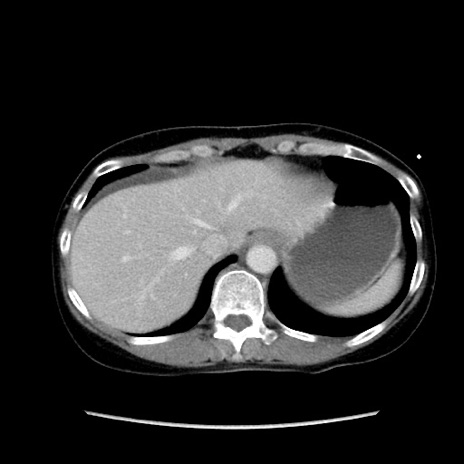

症例32(横断像)

【症例】40歳代 女性

【主訴】上腹部痛、嘔気・嘔吐

【現病歴】約9時間前頃から急に上腹部痛、嘔気、嘔吐が出現。改善しないため救急要請。

【既往歴】子宮頚癌(広汎子宮全摘術、放射線療法)、腸閉塞

【身体所見】腹部:平坦、軟、腸雑音亢進、上腹部を中心に腹部全体に圧痛あり。

【データ】WBC 8400、CRP 0.03